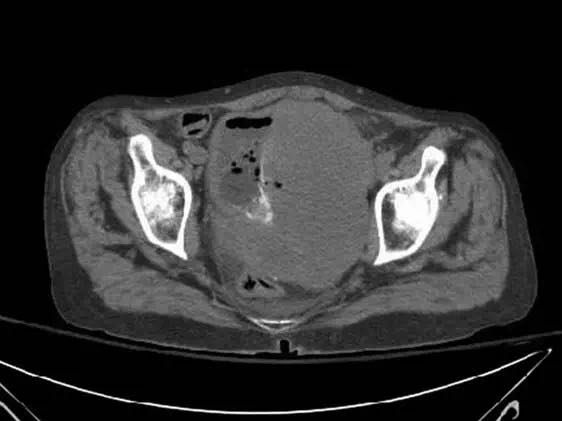

女,62岁,无显著既往史,在家中发现无意识而送医。患者进行紧急插管并就诊于急诊。检查发现患者有肾功能衰竭合并高血钾。胸部X线(图1)显示多发大的结节,高度提示肺转移。胸部(图2)、腹部和骨盆(图3)CT扫描显示毗邻膀胱的盆腔有大肿块,伴双侧肾积水,并有多发较大的空洞肺结节。盆腔肿块活检确诊为高度病变的膀胱移性细胞癌。遗憾的是,病人不接受包括化疗在内的任何侵袭性干预措施,并选择了临终关怀和姑息治疗。 诊断后1个月,患者去世。

通常与弥漫性恶性肿瘤有关。 它们提示预后不良,但偶见报道预后良好的病例。这种典型征象见于肾细胞癌,也见于绒毛膜癌,子宫内膜癌,前列腺癌和一些胃肠恶性肿瘤。但是,与膀胱癌相关的征象罕见。